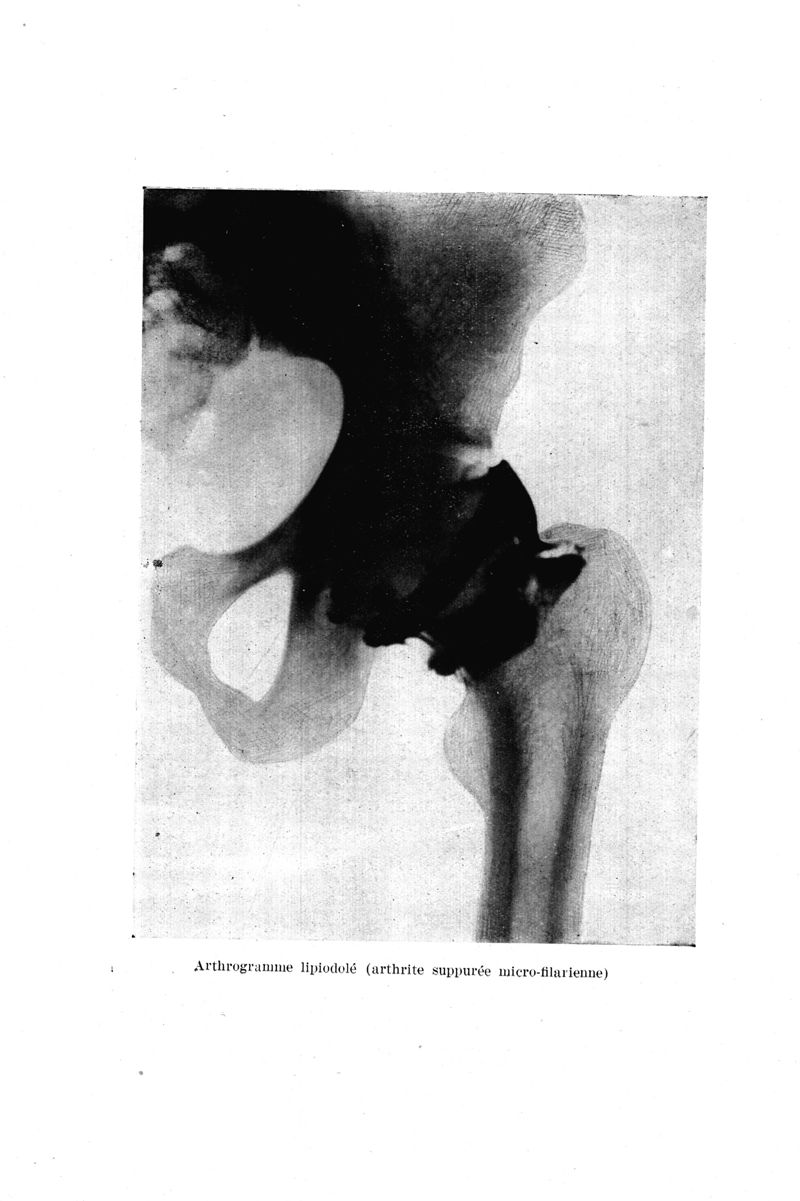

Médecine tropicale : Revue du corps de santé colonial

. - Marseille : Ecole d'application du service de santé des troupes coloniales, 1942.